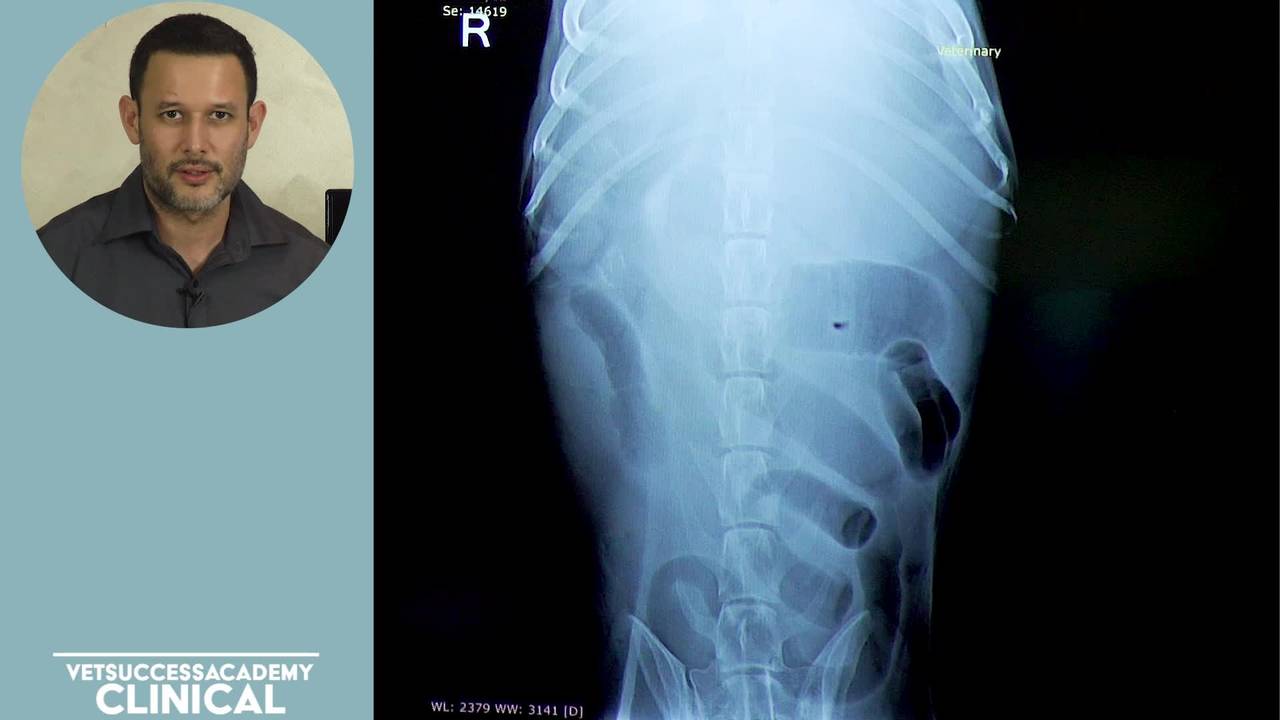

4. Ultrasound

5. Radiography